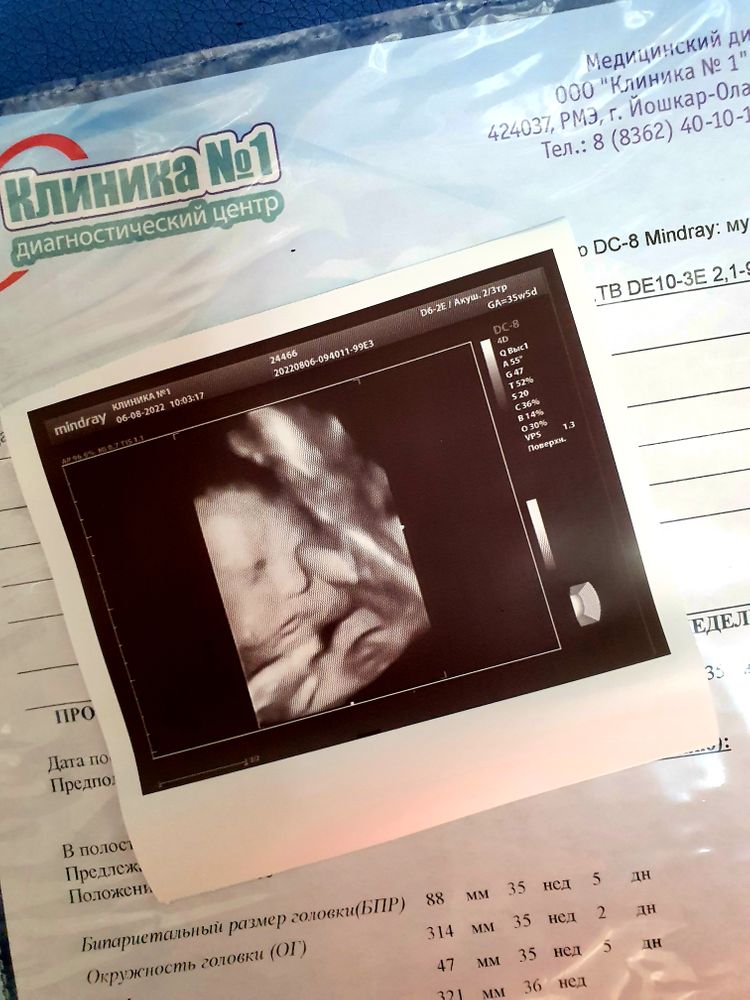

Последнее узи,срок 35+5

Ходила на внеплановое узи, т.к на 3м скрининге было 1.5 кратное обвитие. Очень переживала, хотя узист успокоил, сказал, что для малыша не опасно. И как итог, на сроке 35+5 обвития нет) И, конечно, дали фоточку, уже последнюю, теперь только ждёт наша встреча с малышом🥰 ПКС в 38 недель. Первое фото, это младший сын, на втором, старший. Оба щекастые на фото, хотя в жизни обычные щечки☺️ Разница в возрасте, получается, в 2.9мес